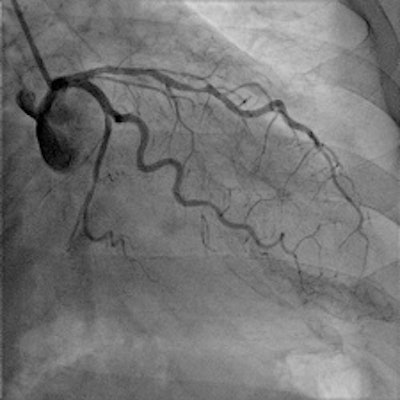

The main advantage for patients is a 50% reduction in total radiation dose through postprocessing of the images obtained by the flat-panel detectors. For one standard adult coronary angiogram, the typical dose used to be 6 to 7 mSv. Cardiologists at the Ghent lab are hoping they will be able to achieve 2 to 3 mSv.

"The quality and innovation of the four main cath lab companies -- Siemens, Phillips, GE, and Toshiba -- are very close, but in our case we chose the Phillips AlluraClarity system due to its radiation dose reduction capabilities," Taeymans said.